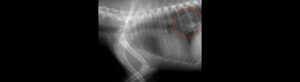

Ο κτηνίατρος θα αξιολογήσει την κατάσταση μέσω κλινικής εξέτασης και, αν χρειαστεί, με ακτινογραφία ή υπέρηχο. Ανάλογα με το αντικείμενο και τη θέση του, η αντιμετώπιση μπορεί να περιλαμβάνει: